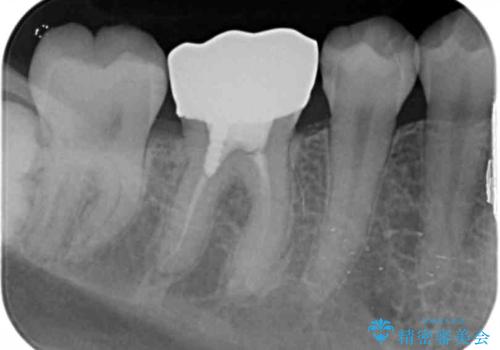

- 他の歯を治療中にレントゲン写真を撮ったところ虫歯を発見。

精度の良いクラウンにやりかえることは今後の虫歯リスクを減らすことにつながります。